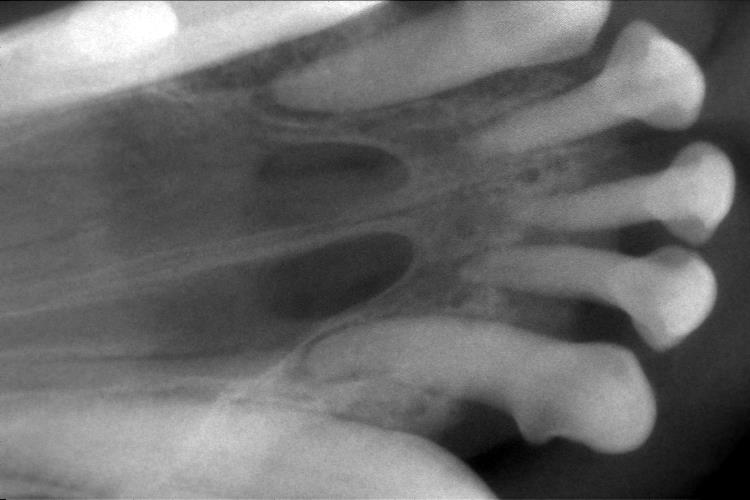

歯科レントゲン検査 ぐらついていた前歯は、歯周病の進行により歯槽骨(歯を支えている骨)が吸収されていました。

写真では歯を支える部分の骨がとても少ないことが分かります。

印をつけた2本は特にぐらつきがひどかったため抜歯処置を行いました。